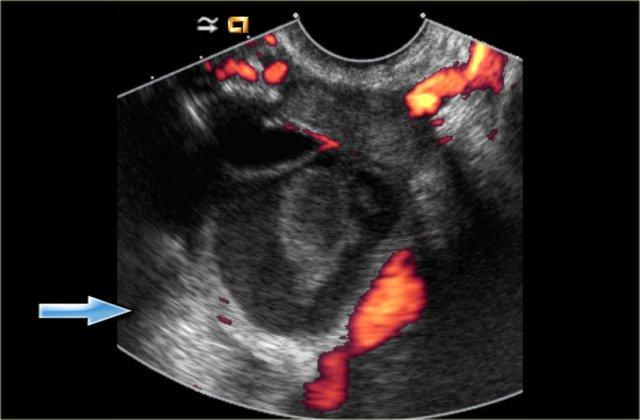

Nang xuất huyết với cục máu đông bắt chước hình ảnh u tân sinh. Lưu ý không có dòng chảy và tăng âm phía sau tốt (mũi tên)

Trong cả hai trường hợp, sẽ không có dòng chảy nội tại trên siêu âm Doppler và có tăng âm phía sau tốt.

Lưu ý có tăng âm phía sau tốt, kể cả qua nang phức tạp (mũi tên xanh).